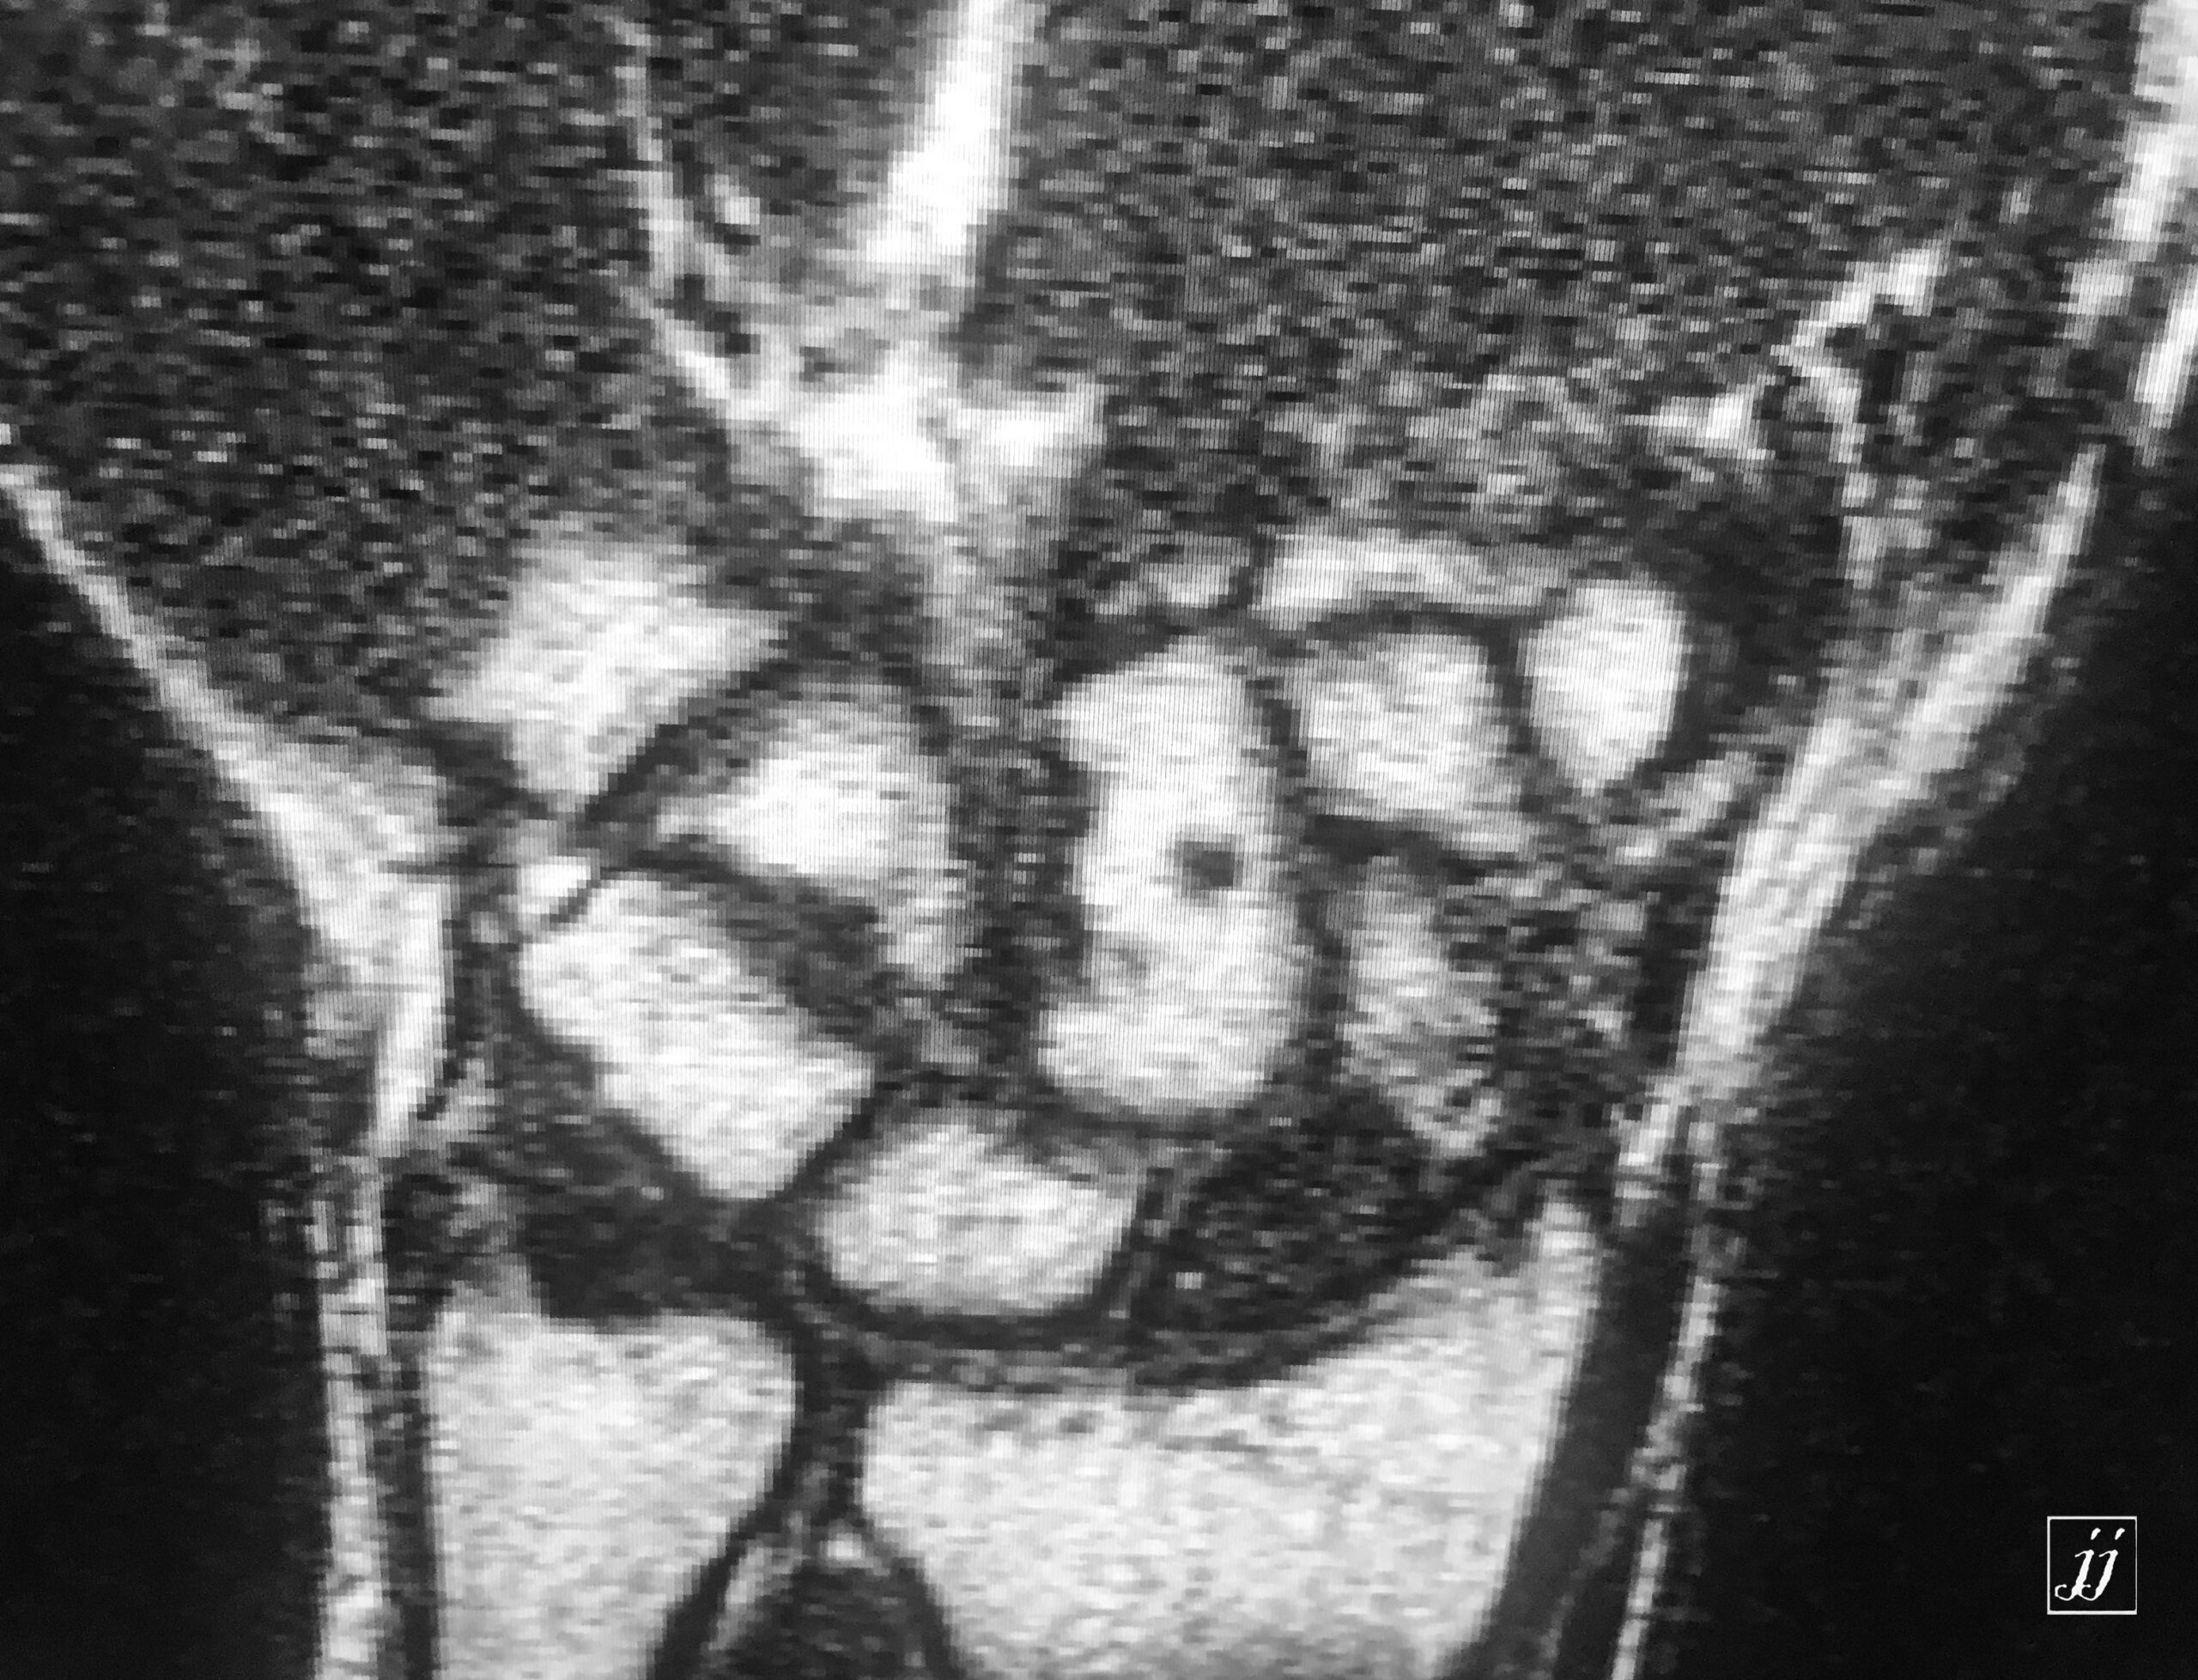

MSK- scaphoid fracture and proximal aVN (5)